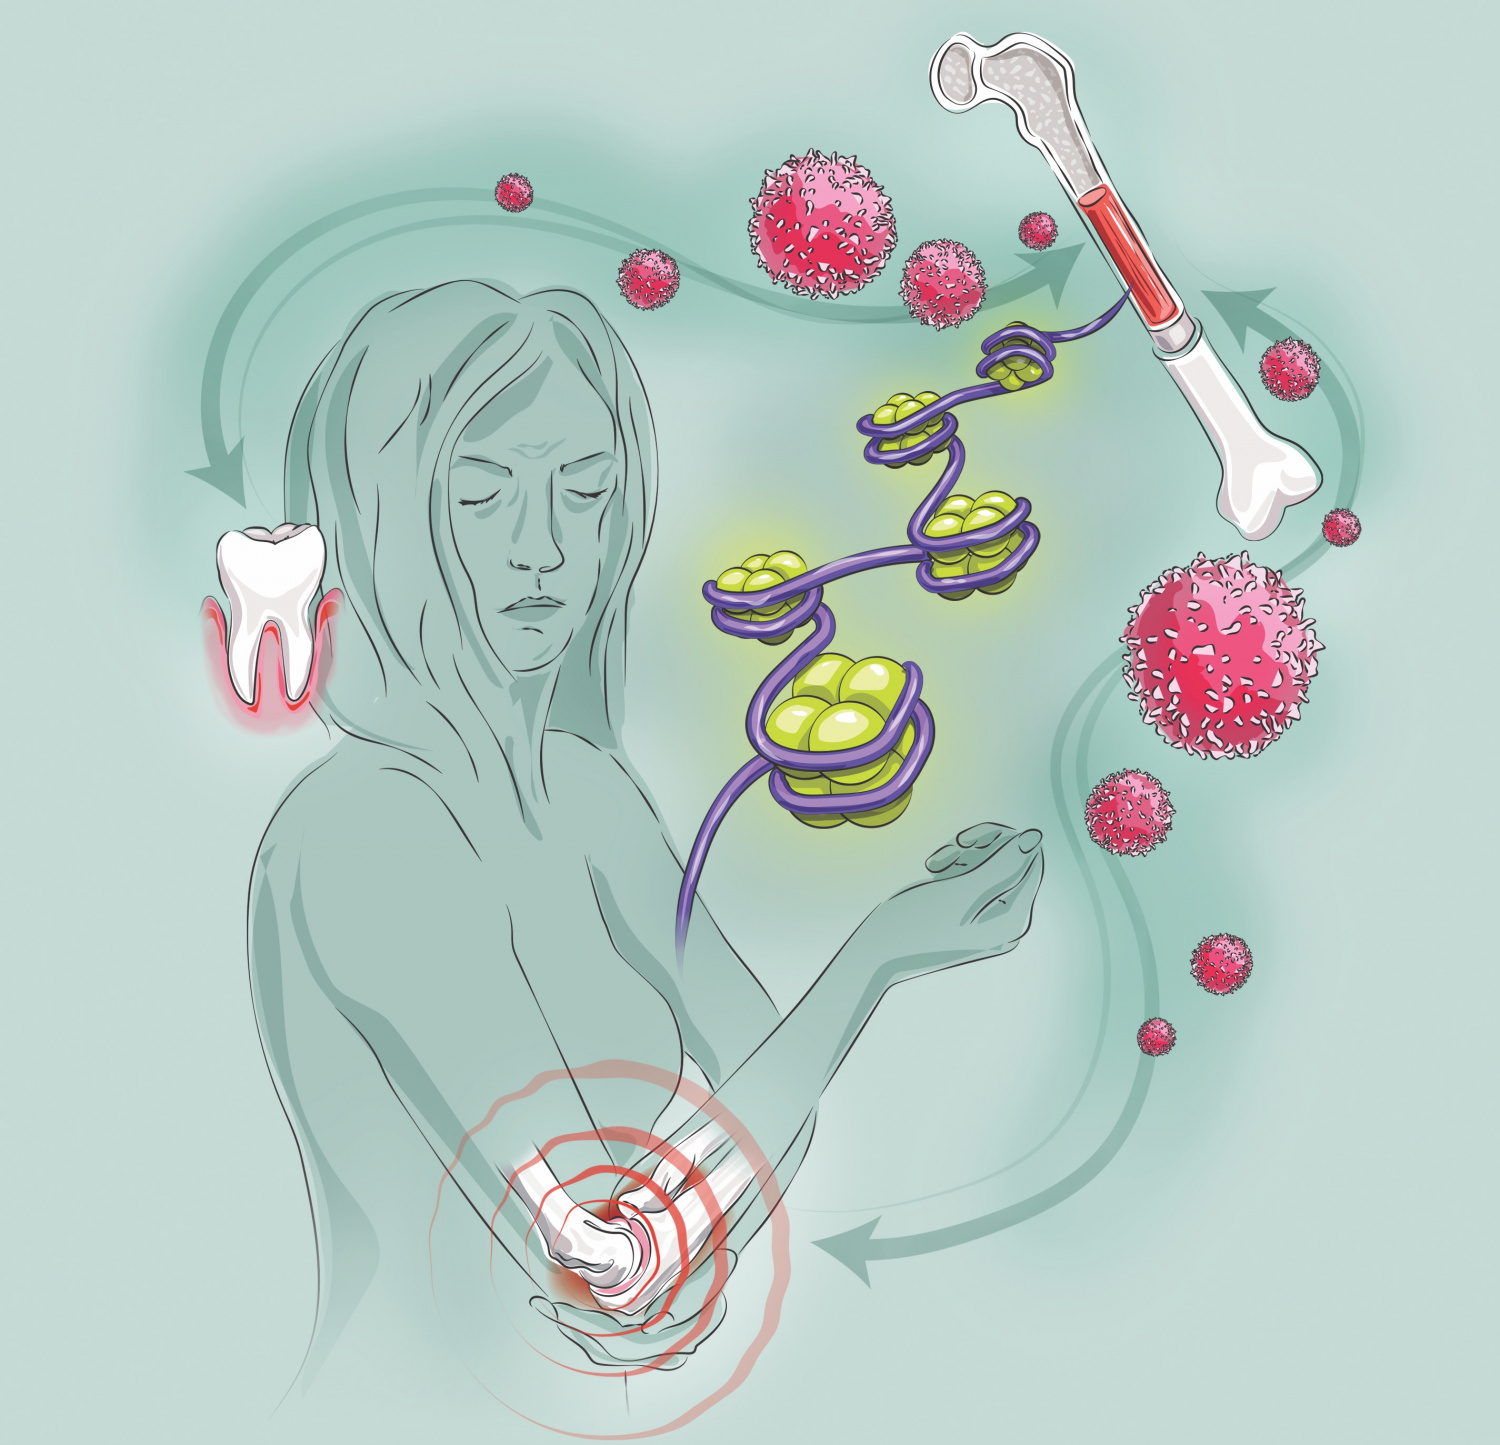

стволовые клетки

трансплантация

иммунитет